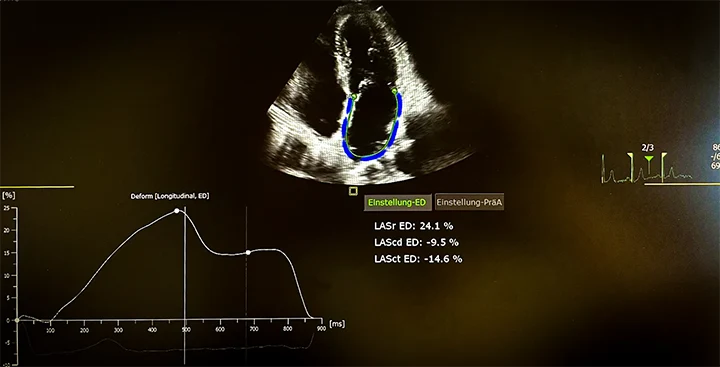

Strain-Analyse (Deformationsanalyse)

Die Strain-Analyse misst die Dehnbarkeit des Herzmuskels – also, wie gut sich das Herz bei jedem Schlag zusammenzieht. Mit modernster Speckle-Tracking-Technologie analysieren wir feinste Bewegungsmuster des Herzmuskels in Echtzeit. So können wir bereits frühzeitig Funktionsstörungen erkennen, bevor sie in anderen Messwerten sichtbar werden.

Typische Einsatzgebiete sind:

- Verlaufskontrollen bei Chemotherapie (kardioonkologische Überwachung)

- Früherkennung bei Amyloidose, Bluthochdruck oder Diabetes

- Beurteilung der Funktion von linker Herzkammer (GLS), linkem Vorhof (LA-Strain) und rechtem Ventrikel (RV-Strain)